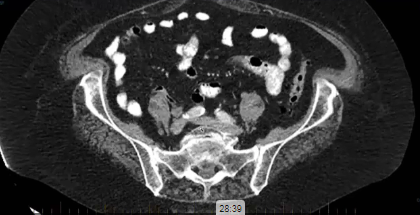

endometrial adenocarcinoma, para-aortic nodes, PET CT, diabetes, charcot arthropathy, groin nodes, pelvis, negative cervical margins, cisplatin, small bowel, Harkenrider, contouring, MRI, tumor, vaginal bleeding, relapse, persistence, cylinder, dose distribution, dosimetry, brachytherapy, fractio...

squamous cell carcinoma, dysplasia, PET, SIB, brachytherapy, endocervical, MRI, nodal location, inguinofemoral, right external iliac, CTV, deescalation, dosimetry, sigmoid, hysterectomy, concurrent chemoradiation, stenotic cervix, abdominal infection, external planning, avoid structure, antibioti...

chemotherapy, radiation therapy, sandwich regimen, brachytherapy, well differentiated endometrioid adenocarcinoma, neoadjuvant chemotherapy, small bowel, dilation, dosimetry, gross disease dose, MRI, cirrhosis, external beam radiation, Rotte Y applicator, CT scan, dual tandem, 3-D printing, endom...